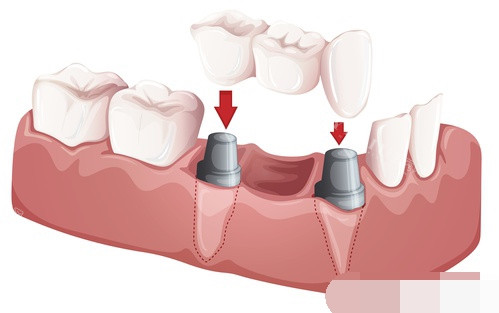

一、种植牙价格

种植牙是很多牙齿缺失患者的理想选择。以下是常见的种植牙价格:

国产威高 WEGO 种植牙:5000 元起

国产百康特种植牙:6000 元起

韩国登腾种植牙:4999 元起

韩国奥齿泰种植牙:7500 元起

瑞士士卓曼种植牙:7880 元起

瑞典诺贝尔种植牙:7880 元起

德国 ICX 种植牙:8980 元起

法国安卓健种植牙:11000 元起

瑞士 ITI 亲水种植牙:13800 元起